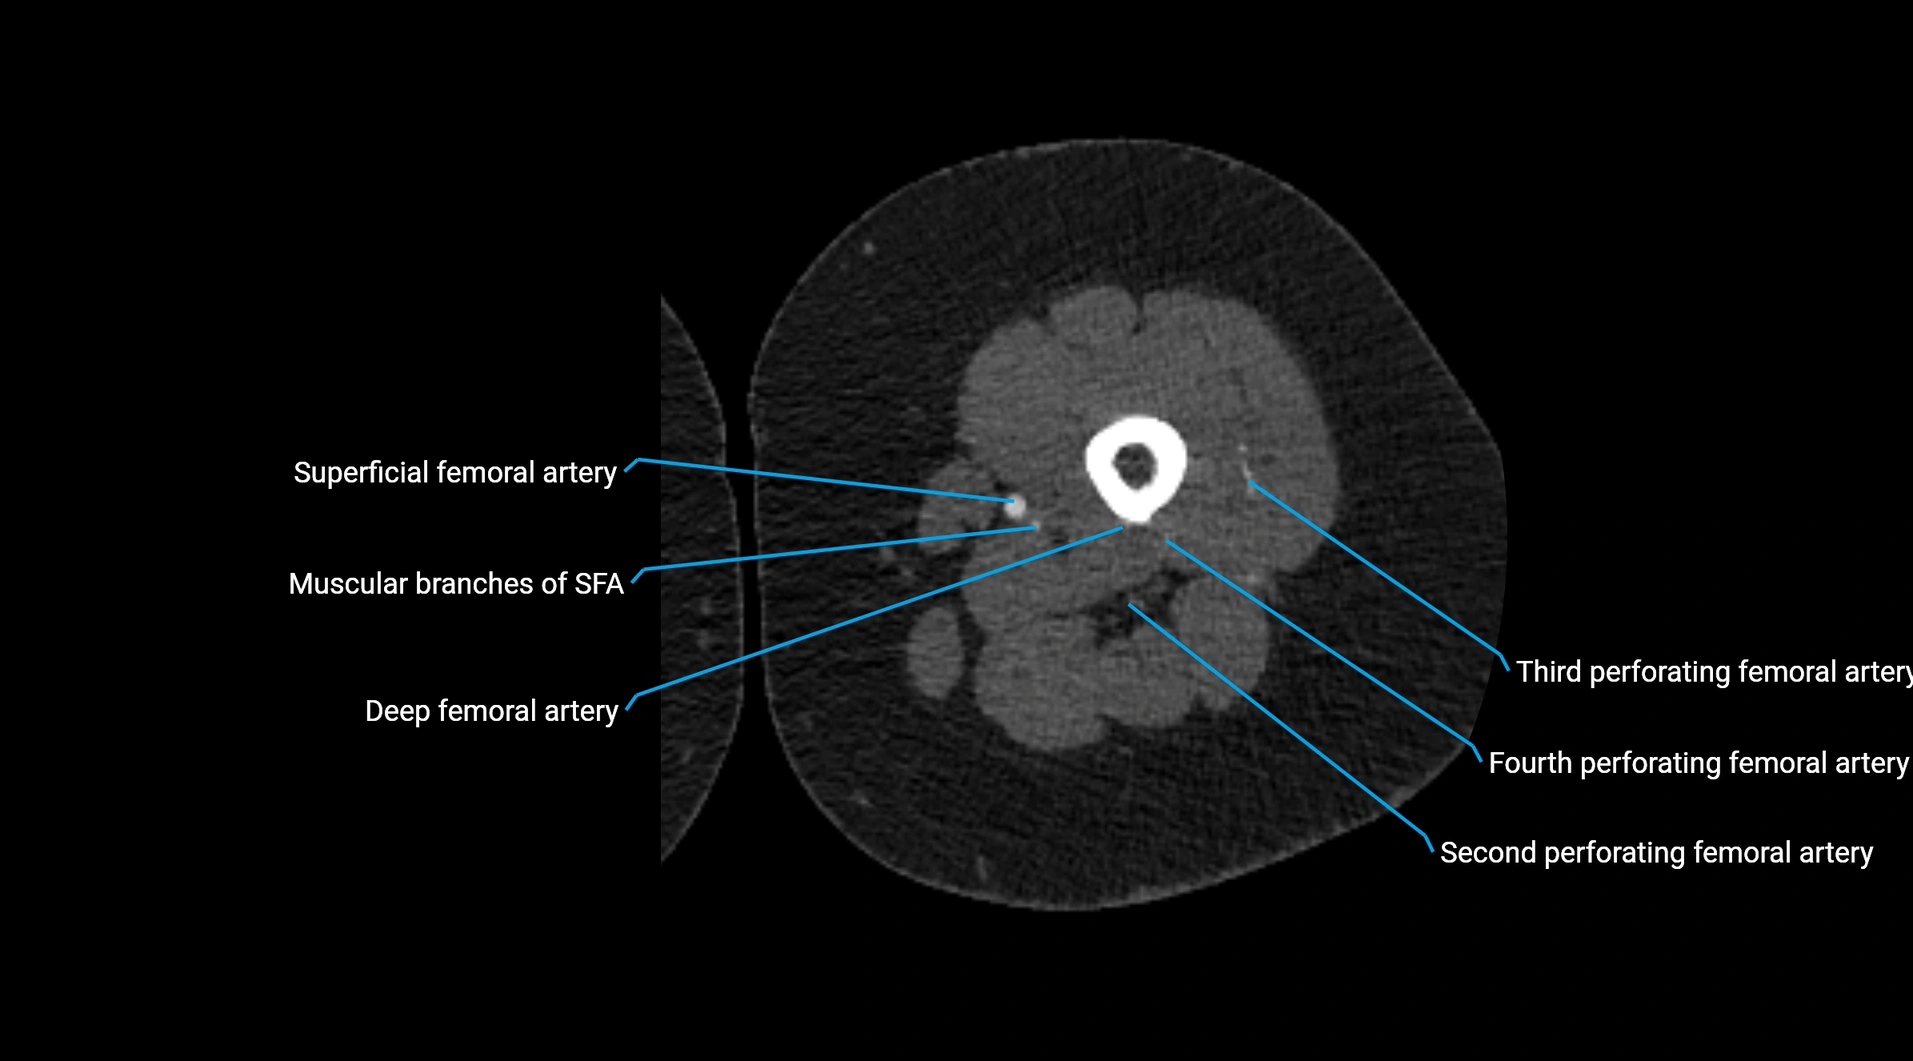

CT images

image